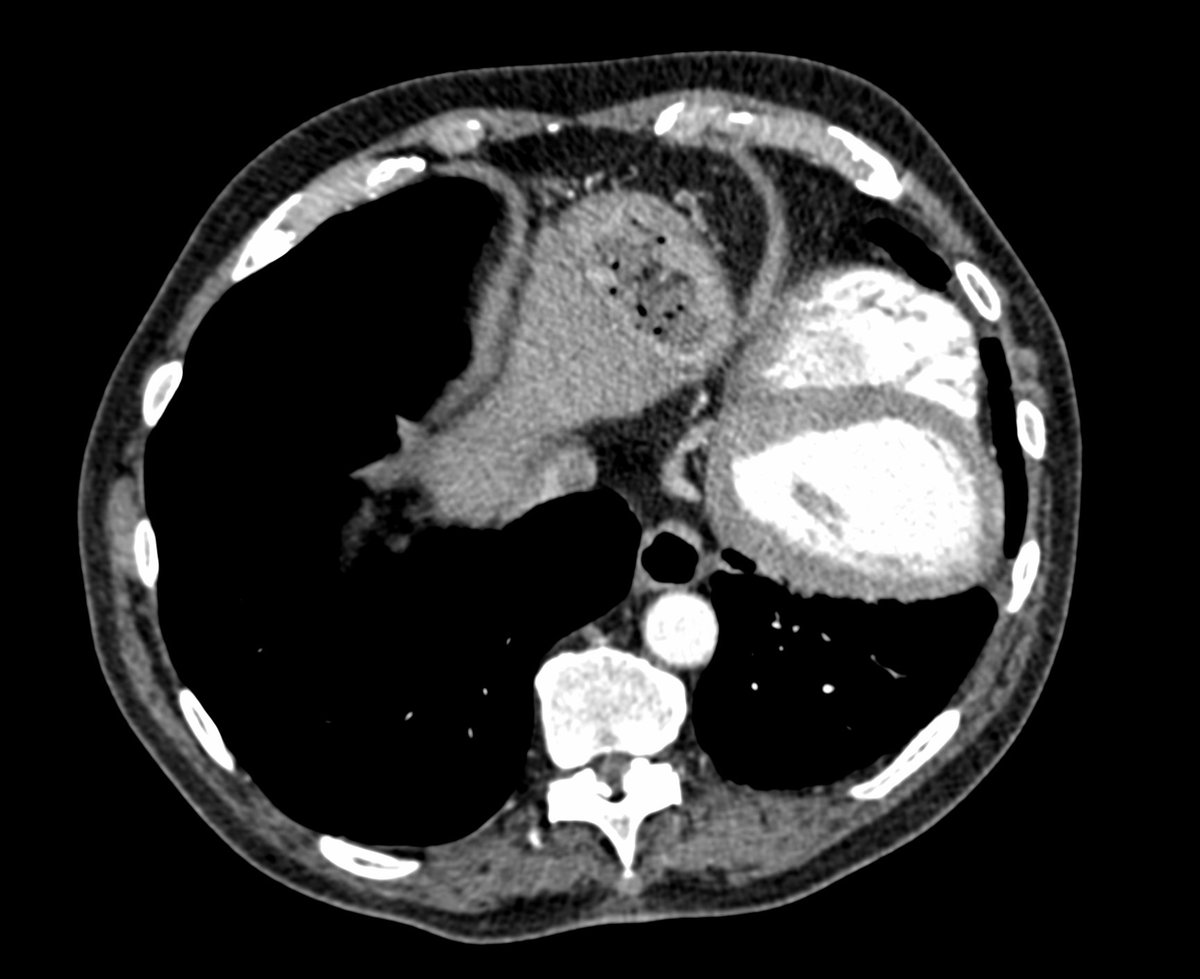

Friday conundrum. Routine chest radiograph and subsequent CT Thorax. Can you see anything abnormal on these images? Can you put it all together? Answers tomorrow.

#FOAMrad#FOAMed#FRCR#radiology#radiologists#CardioEd#cardiotwitter#RadRes#RadReg#meded Have a good weekend! pic.twitter.com/bkLPj1BPTa